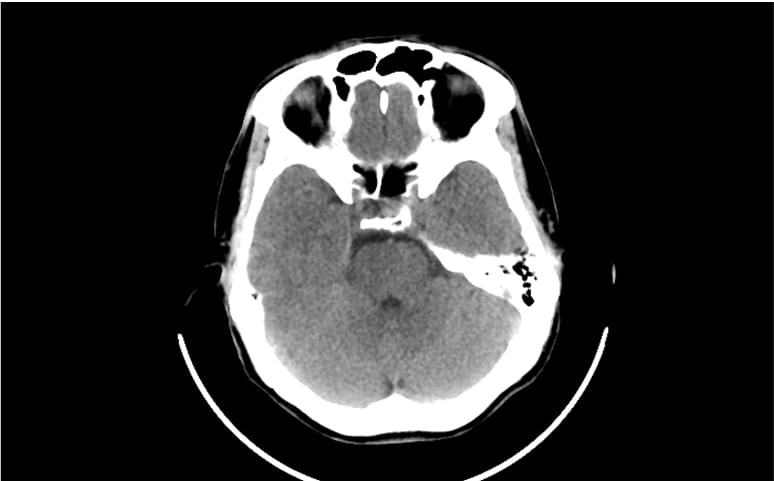

Clinical decision-support for complications from treatment

Cancer treatments, including chemotherapy, immunotherapy and radiation, can cause acute or chronic side effects, that may require clinical management, such as sepsis, congestive heart failure (CHF) and vertebral compression fracture (VFF).

- Leverage comprehensive AI tools to detect a wide range of findings on CXR, including sepsis, CHF and VFF to accelerate the care pathway.